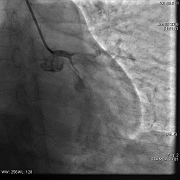

冠脉造影(右冠)

◆左主干未见斑块及狭窄,前降支近段可见斑块,狭窄约50-60%,中段分出第二对角支后完全闭塞,血流Timi0级,回旋支中段及远段斑块,狭窄约80-90%,血流Timi3级,右冠全程管壁不规则,斑块狭窄约30-40%。